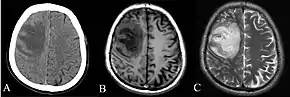

Various imaging modalities can also help with the diagnosis of melioidosis. In acute melioidosis with the spreading of the bacteria through the bloodstream, the chest X-ray shows multifocal nodular lesions. It may also show merging nodules or cavitations. For those with acute melioidosis without the spread to the bloodstream, chest X-ray shows upper-lobe consolidation or cavitations. In chronic melioidosis, the slow progression of upper-lobe consolidation of the lungs resembles tuberculosis. For abscesses located in other parts of the body apart from the lungs, especially in the liver and spleen, CT scan has higher sensitivity when compared with an ultrasound scan. In liver and splenic abscesses, an ultrasound scan shows "target-like" lesions, while CT scan shows "honeycomb sign" in liver abscesses. For melioidosis involving the brain, MRI has higher sensitivity than a CT scan in diagnosing the lesion. MRI shows ring-enhancing lesions for brain melioidosis.[9]